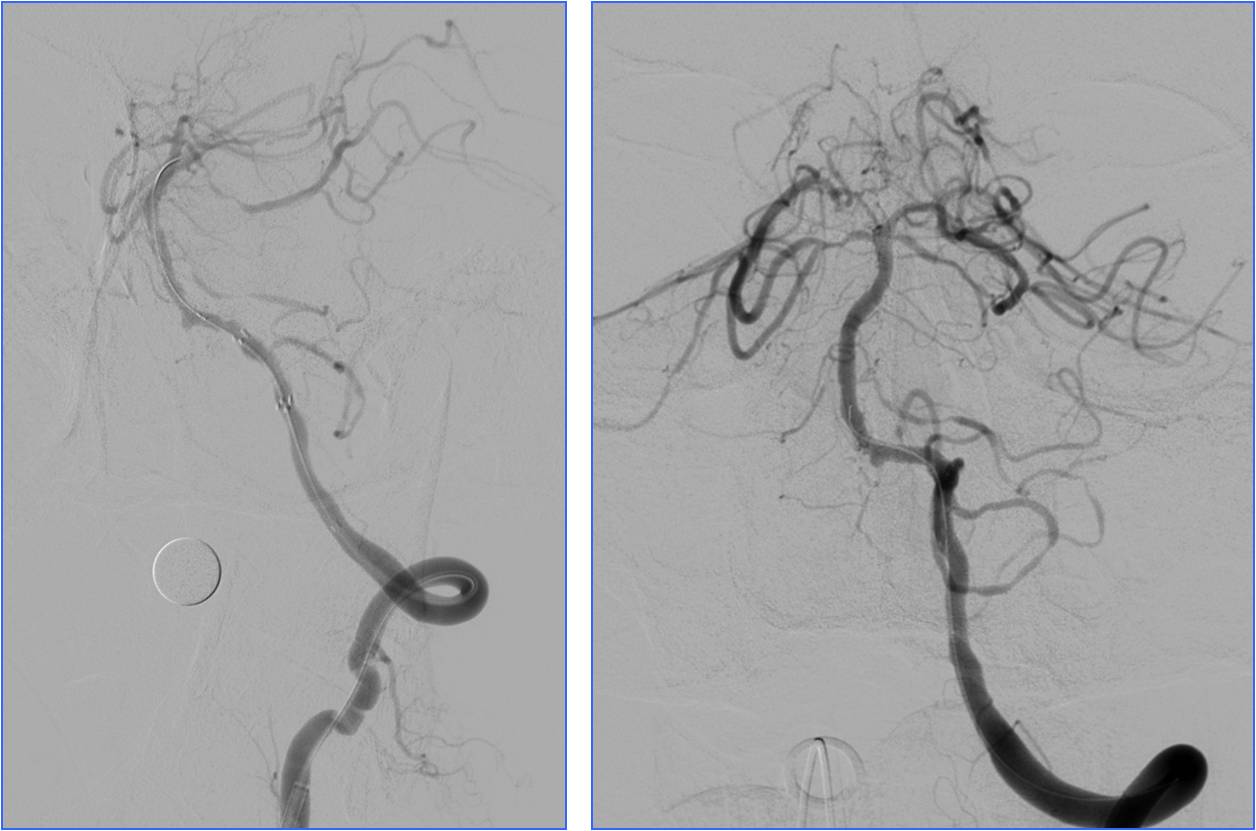

Case1 全麻插管时机选择

》男,60岁。有房颤史。

》7:50三次TIA(发作性右侧肢体无力),8:45到我院急诊,8:52完成头CT检查。

》9:30再次加重,11:30通知介入医师。

》NIHSS评分10分。

》12:20股动脉穿刺。

》12:50血管再通。

》10天后出院,NIHSS 0分。

》全身麻醉。

▼左侧大脑中动脉高密度征

▼气管插管时机:释放支架重建血流后

术前静脉溶栓

术中动脉溶栓

心源性栓塞出血转化